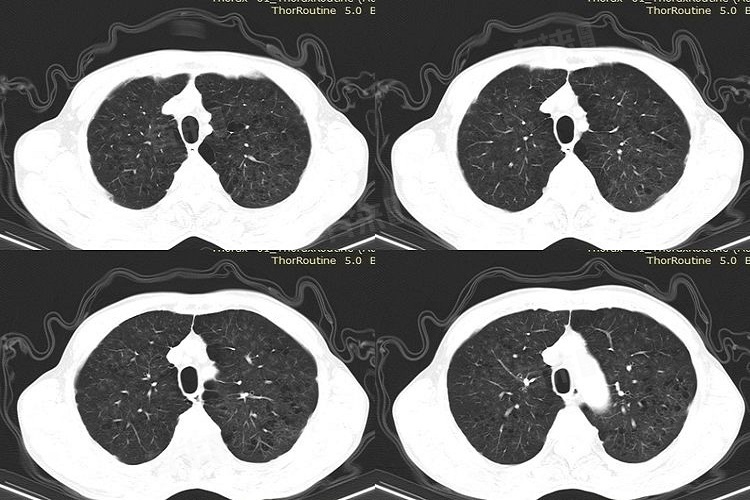

2、了解片子的构成

- 肺部CT片子通常包括肺窗和纵隔窗两种图像,肺窗主要显示肺部的结构和病变。纵隔窗主要用于观察纵隔内的软组织、血管、淋巴结等。

3、观察肺窗图像

- 注意肺纹理是否清晰,气管、支气管的走行是否正常。观察肺内是否有异常的密度影,如磨玻璃影、结节影等,这些可能是炎症、肿瘤等病变的表现。留意是否存在气胸、肺不张等病变情况。